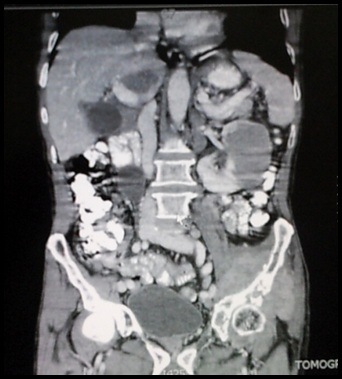

Caso Clínico: Paciente masculino de 64 años de edad que inicia con cuadro de dolor costolumbar bilateral, de intensidad 5/10, tipo cólico, irradiado a ambos flancos abdominales acompañado de parestesias en ambos miembros inferiores desde hace ±10 meses. Posteriormente, refiere presentar astenia, adinamia, anorexia, dolor somático permanente de intensidad 5/10 de localización en pelvis, columna sacra, lumbar, extremidades inferiores y debilidad muscular. Se realiza TAC abdominopélvico que evidencia masa sólida homogénea, única, de 8x7x7 cm en riñón izquierdo con metástasis ósea, hepática y esplénica. El estudio histopatológico muestra Linfoma B Difuso de células grandes.

Discusión: El paciente presentó un inicio rápido de síntomas relacionados con una masa renal que al ser estudiada radiológicamente confirmó una gran lesión renal sólida con compromiso de lesiones pequeñas en hígado, bazo y nódulos paraaórticos, sugiriendo que el órgano primario comprometido es el riñón izquierdo. Inicialmente se consideró un posible diagnóstico de Carcinoma de células renales metastásico, debido a la clínica y la epidemiología, por lo que se le realiza una nefrectomía radical izquierda. Sin embargo, el estudio histopatológico e inmunohistoquímico reveló un Linfoma B difuso de células grandes en estadio IV B.